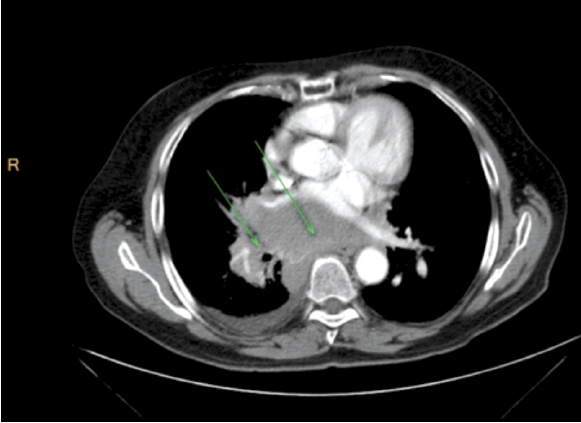

Ответ на терапию оценивался по данным мультиспиральной компьютерной томографии (МСКТ) по двум таргетным очагам: образование в корне правого легкого размерами 93×85×119 мм (очаг №1), конгломерат увеличенных внутригрудных лимфоузлов размерами 65×72×118 мм (очаг №2); рис. 1.

Рис. 1. Пациент 1934 г. р. МСКТ органов грудной клетки с внутривенным контрастированием, сентябрь 2017 г. (до начала лечения).

Fig. 1. The patient, born 1934. MSCT of the chest cavity with contrast, September 2017 (before the treatment).